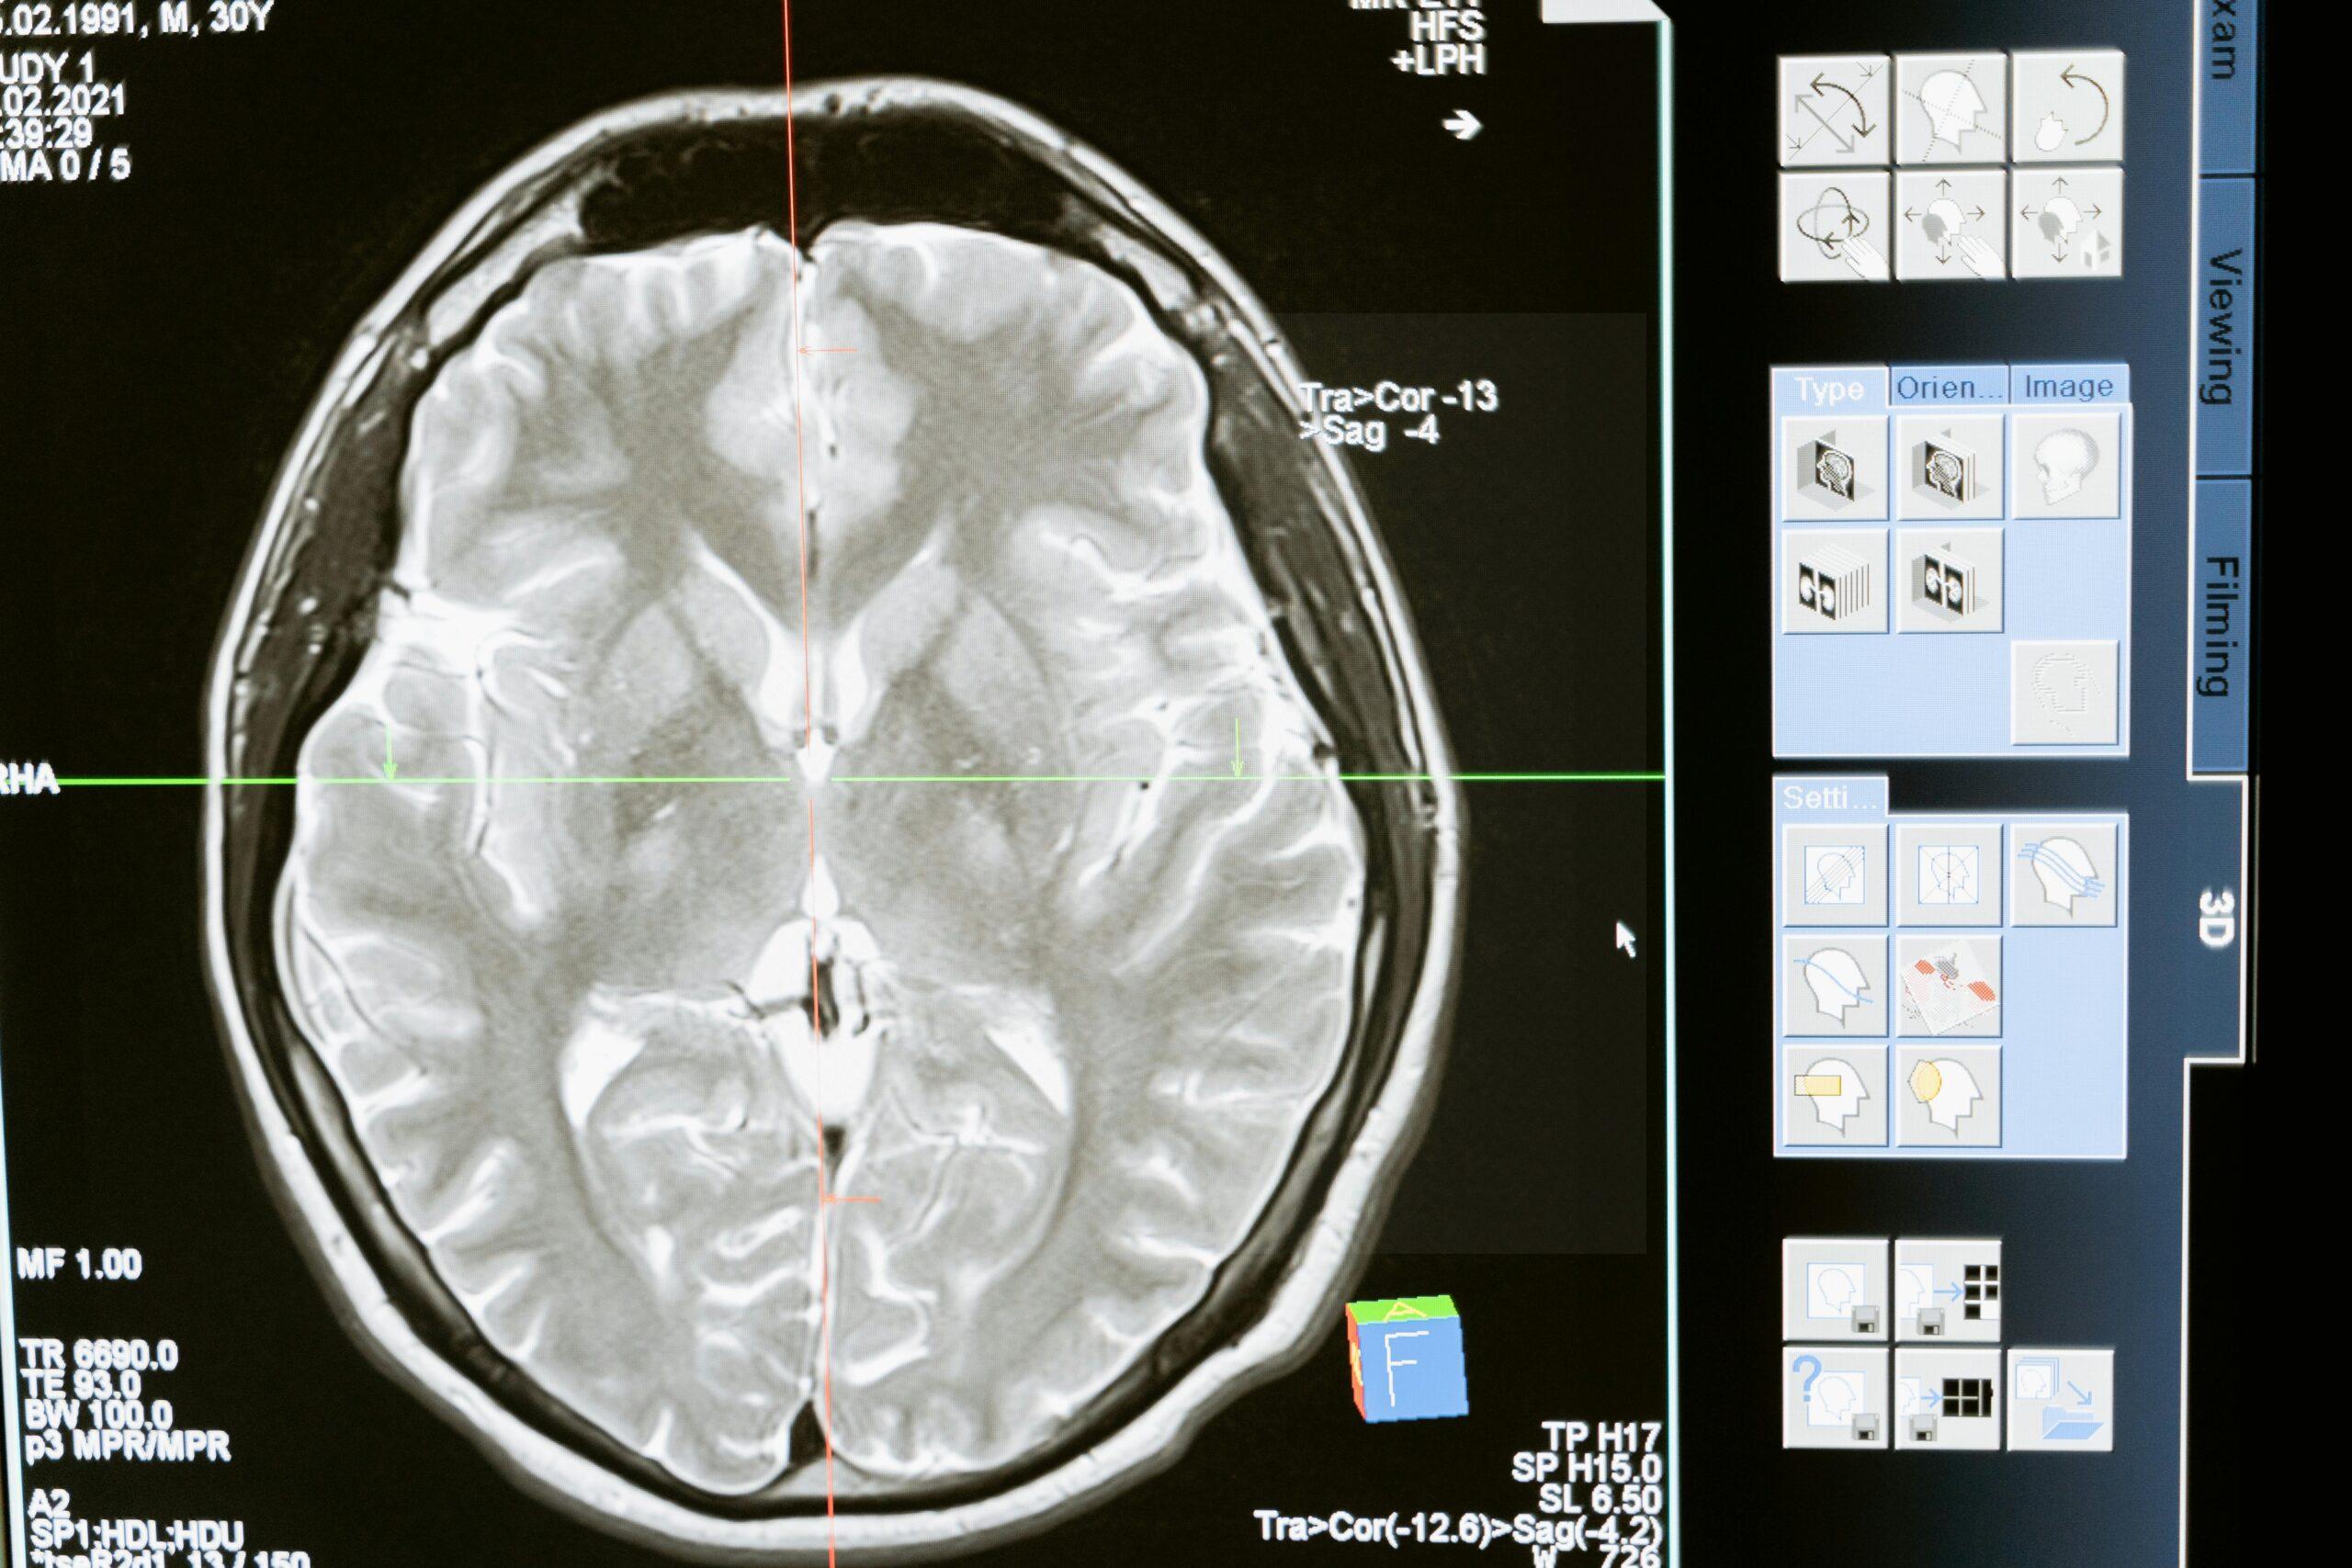

2. Overnight polysomnography (PSG)—an in-lab sleep study to rule out other causes like obstructive sleep apnea, which can also cause daytime sleepiness.

5. Blood tests and imaging—sometimes used to exclude other conditions or look for secondary causes.